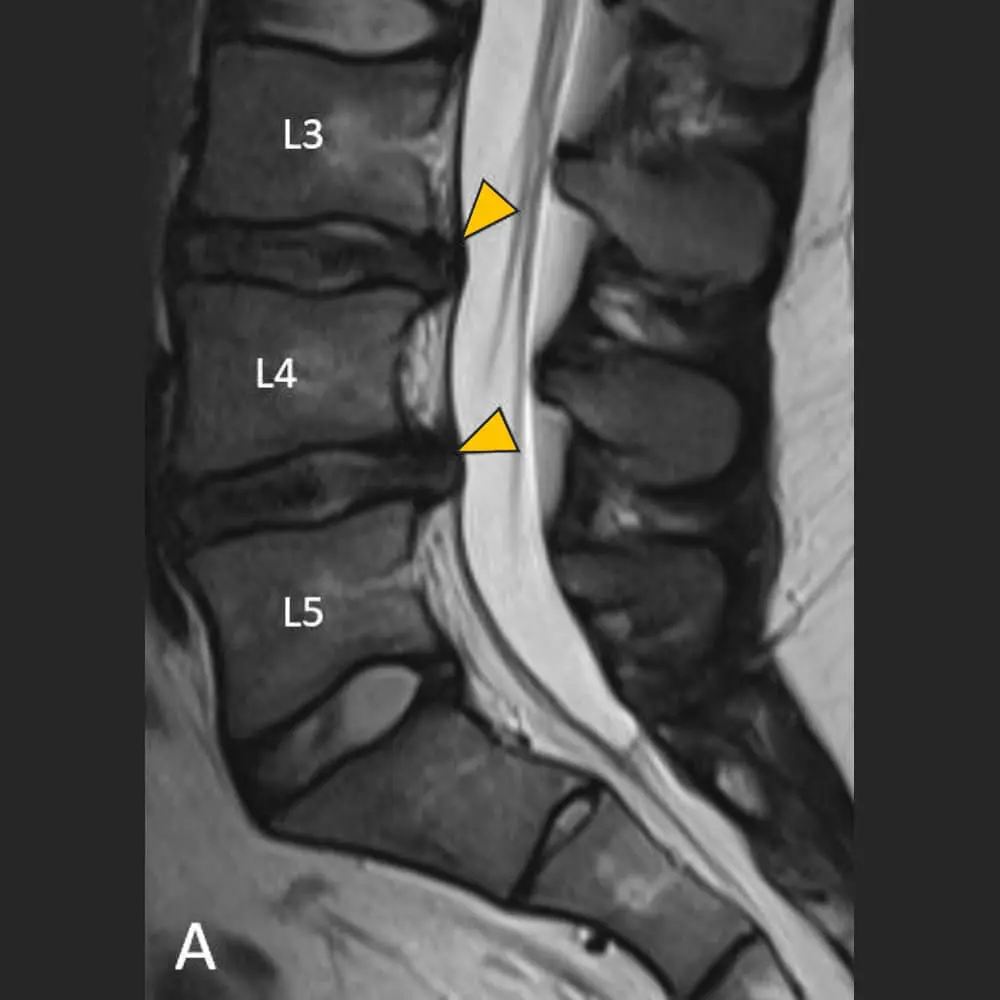

- Bildgebung: MRT = Methode der Wahl

- Prolapse: Verlagerung von Bandscheibengewebe (Nucleus pulposus) durch Anulus fibrosus → Nervenwurzelkompression

- LWS (90 %): L4/L5, L5/S1

- Mediolateral (90 %): untere Wurzel betroffen (z. B. LWK4/5 → L5)